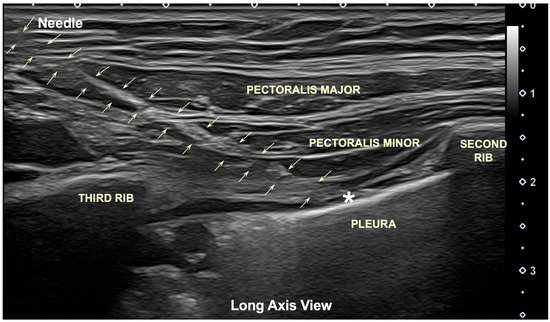

Cadaveric and Ultrasound-Guided Evaluation of Two Needling Approaches Targeting the Pectoralis Minor Muscle: A Pilot Feasibility Study

by José L. Sánchez-Sánchez, Pedro Belón-Pérez, Xavier Grevol-Coll, Miguel Robles-García, Gustavo Plaza-Manzano, César Fernández-de-las-Peñas and Laura Calderón-Díez

Background: The pectoralis minor muscle can be a source of musculoskeletal-related chest pain by contributing to thoracic outlet syndrome. Needling interventions applied to chest wall muscles have an inherent risk of puncturing sensitive structures, e.g., the pleura. Objective: The objective of [...] Read more.

Background: The pectoralis minor muscle can be a source of musculoskeletal-related chest pain by contributing to thoracic outlet syndrome. Needling interventions applied to chest wall muscles have an inherent risk of puncturing sensitive structures, e.g., the pleura. Objective: The objective of this study was to preliminarily investigate the safety and accuracy of two needling approaches targeting the pectoralis minor muscle. Methods: A pincer- and flat-needle approach targeting the pectoralis minor muscle was conducted in five Thiel-embalmed cadavers and 10 healthy volunteers by an experienced and a novice clinician. The needle was inserted until the clinician considered that the pectoralis minor muscle was reached. Each clinician conducted 10 needle insertions with each approach. In cadavers, the accuracy of needle placement was identified with both ultrasound imaging and anatomical dissection. In healthy volunteers, needle placement accuracy was evaluated with ultrasound imaging. Results: Accurate needle penetration of the pectoralis minor muscle was 80–90% and 40–70% for experienced and novice clinicians, respectively, with the pincer approach. One pleural puncture was observed in one cadaver specimen with this approach by the novice clinician. Accurate needle penetration of the pectoralis minor muscle was 100% and 90% for experienced and novice clinicians, respectively, with the flat approach. The novice clinician required 3.5 times longer to perform the flat approach than the experienced clinician. Conclusions: The results of this pilot feasibility study suggest that a pincer-needle approach seems to be less accurate than the flat-needle approach and substantially more error-prone for a novice clinician, which, in a clinical context, could pose a potential risk of pneumothorax based on the pleural puncture observed in one cadaver specimen. In contrast, our preliminary results revealed that the flat-needle approach could have better accuracy and safety, particularly when performed under real ultrasound guidance. Full article